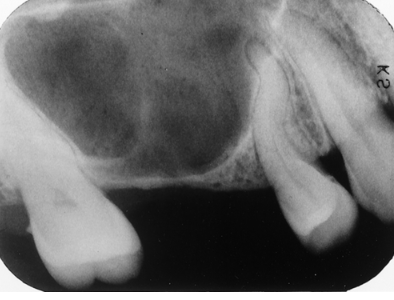

Note the dilacerated premolar root. The condition that affects this sinus is

pneumatization